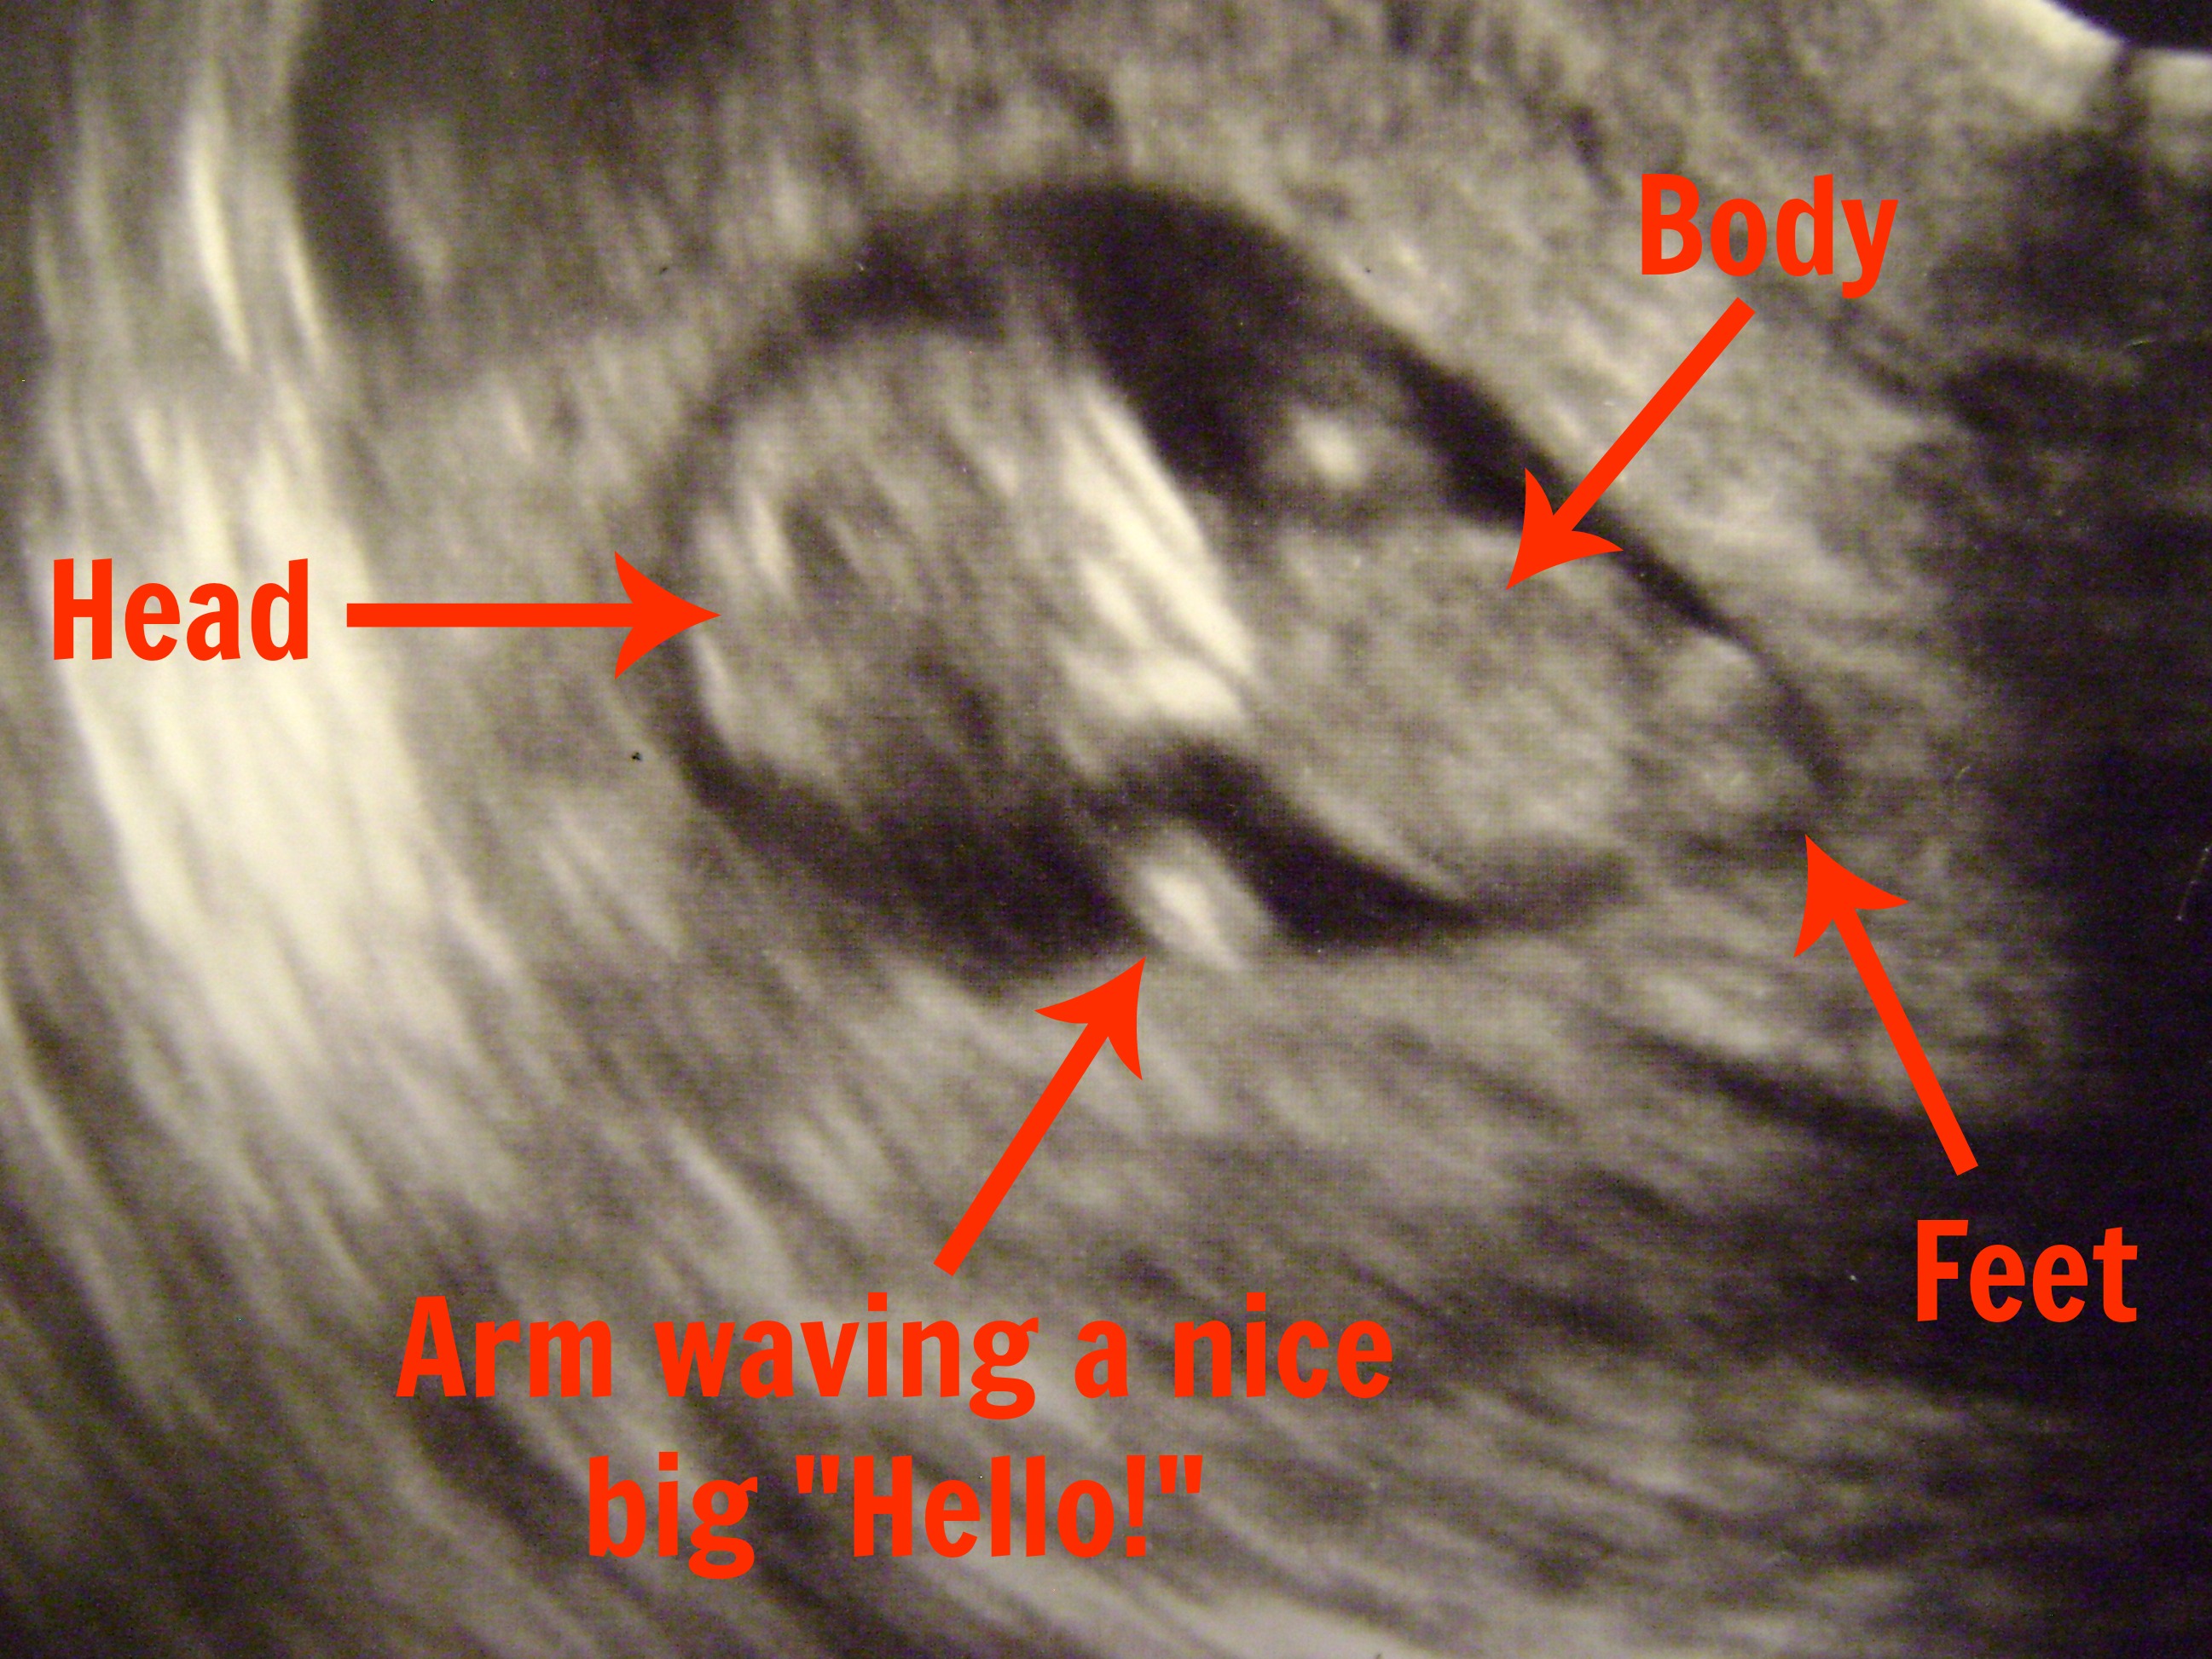

You see…….there is a little alien looking creature growing inside me right now! And for two months it was zapping me of energy and causing me to lay on the couch hoping that the horrible nauseous feeling would go away.

Yep, that’s right! We are expecting baby #2 the beginning of February and this guy is going to be a big brother!